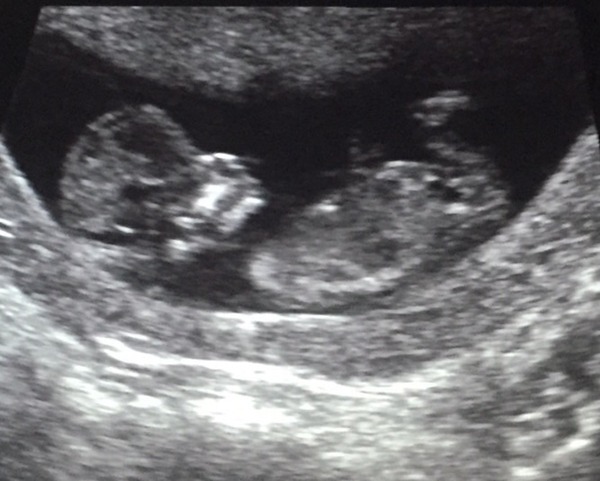

I've just had my 12 week scan Grin

All is looking fine, the baby was having a right old wriggle around but they managed to get all the measurements they needed. The nuchal measurement was fine but obviously we need to wait for the blood test results before we will get told if low or high risk. Baby was measuring 11+4 which I was kind of expecting based on when I think I ovulated but they said they don't change your due date unless it's more than 5 days out which it wasn't. So happy and relieved now!

Me624 · 21/08/2015 09:32

Oh and here's a pic Smile

Awww fantastic news, what a gorgeous pic!! I'm 11+5 going by LMP but scan isn't until September 2nd! So what is your due date?

I had a private scan at 8+1 which just looked like a blob so I'm really pleased it looks like a proper baby now!

I love seeing these scan pics, the difference between the 8/9 & 12 weeks is astonishing.